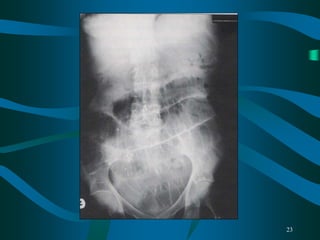

• What kind of X-ray is this?

• What does it show?